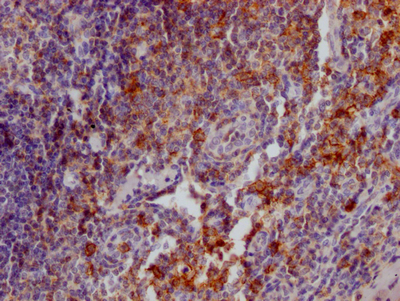

IHC image of CSB-RA567010A0HU diluted at 1:100 and staining in paraffin-embedded human tonsil tissue performed on a Leica BondTM system. After dewaxing and hydration, antigen retrieval was mediated by high pressure in a citrate buffer (pH 6.0). Section was blocked with 10% normal goat serum 30min at RT. Then primary antibody (1% BSA) was incubated at 4℃ overnight. The primary is detected by a Goat anti-rabbit IgG polymer labeled by HRP and visualized using 0.05% DAB.